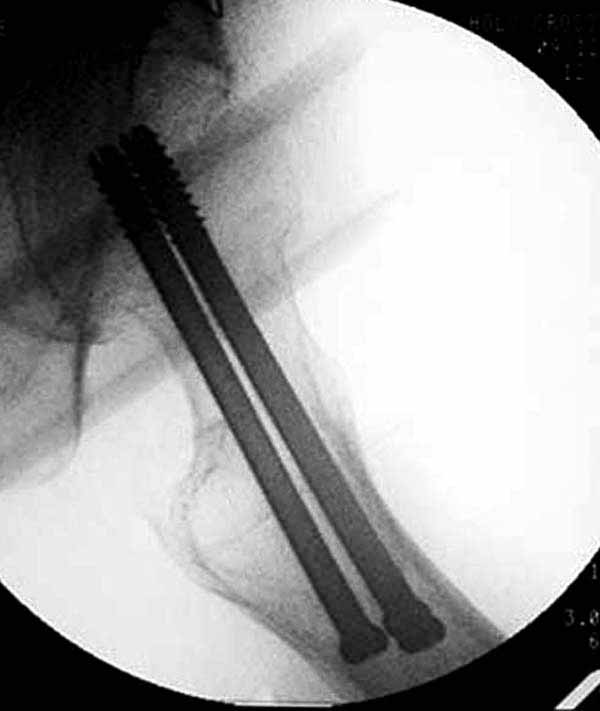

Пациентка Ш. 76 лет, 11 дней назад прооперирована по поводу вколоченного субкапитального перелома шейки левой бедренной кости, 3-мя канюлированными винтами. Вчера пациентка упала в палате. И вот результат- подимплантатный подвертельный перелом левой бедренной кости. Уважаемые коллеги, пожалуйста посоветуйте какой метод дальнейшего лечения предпринять дальше.Соматически пациента повышенного питания, страдает варикозной болезнью нижних конечностей.Из предложенных вариантов коллег - целллокастовая укороченная кокситная повязка, скелетное вытяжение сроком на 40-45 суток - отпали сразу, так как необходимо активизация пациентки.На данный момент рассматриваем следующие варианта реостеосинтеза:(наличие технических возможностей) 1. Длинная Gamma 3 Stryker (с предварительной интраоперационной фиксацией головки спицами).2. Трохантерный штифт DePuy с 2-мя метафизарными винтами в проксимальном отделе, (также с интраоперационной фиксацией головки спицами. Очень настораживает стабильность фиксации с проксимальном отделе с связи с выборкой костной ткани ранее находящимися там канюлированными винтами. Сейчас пациентка находится на скелетном вытяжении, с дисциплинирующим грузом. Операция планируется после праздников. Заранее извиняемся за качество и неполное соответствие проекций на R-ммах (R-служба отдельная песня). При интраоперационном ЭОП-контроле винты в аксиальной проекции разнесены по шейке.

Как отметили коллеги, необходимо обратить внимание на последовательность введения каннюлированных шурупов. Рекомендуется введение в форме “V”, т.е основанием вниз, потому что в другой последовательности за счет увеличения стресса латерального кортекса имеется риск перелома. За редким исключением удается установить Guide wire с первой попытки и многоразовые пробы спицей увеличивают стресс. Небольшая травма может привести к перелому.

Работа Burstein AH and Wright TM: Fundamentals of Orthopaedic Biomechanics. Williams & Wilkins, Baltimore, pp. 160-169, 1994 доказывает, что шурупы, введенные на уровне малого вертела или ниже, приводят к осложнению. Введенные шурупы под 135 и больше градусов в 20% осложнились подвертельными переломами бедра.